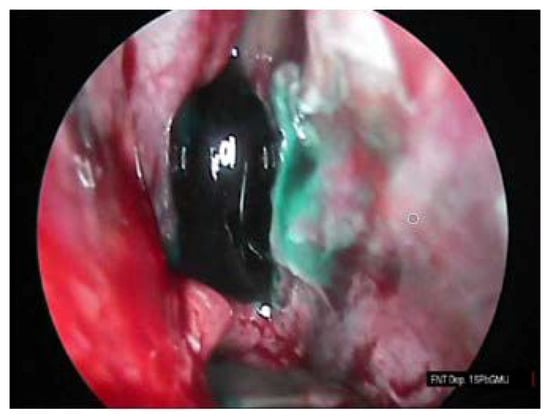

The procedure of the sphenoid sinus volume based on CT scanning followed by 3D reconstruction is illustrated in Figure 1. The corresponding intraoperative measurement procedures are illustrated in Figure 2, Figure 3 and Figure 4.

Figure 3. Colored mucosa of the sphenoid sinus.